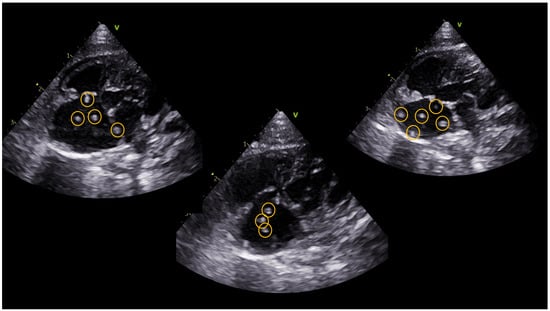

The ferret underwent a conventional transthoracic echocardiographic examination using a 12 MHz phased array ultrasound machine (Vivid IQ, General Electric, Boston, MA, USA). Echocardiographic findings included the presence of multiple parallel hyperechoic “equal signs” in the right atrium, indicating the presence of adult heartworms (Figure 1) [3,6]. Moderate dilatation of the pulmonary trunk, right atrium, and right ventricle was demonstrated with the presence of tricuspid regurgitation with a maximum velocity of 3.08 m/s (Table 1) [8].

Figure 1. Visualization of multiple parallel hyperechoic “equal signs” in the right atrial cavity, consistent with adult Dirofilaria immitis, using a left parasternal 4-chamber apical echocardiographic view.